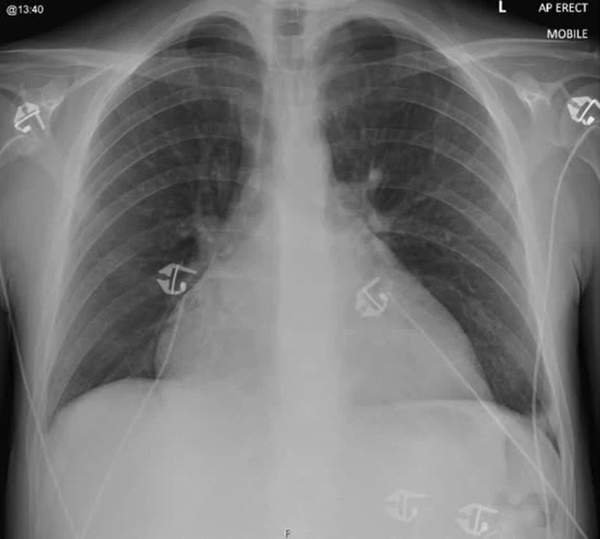

Tình trạng bóng tim mở rộng có thể nhìn thấy trên X-quang ngực (Ảnh: Báo cáo Ca bệnh BMJ).